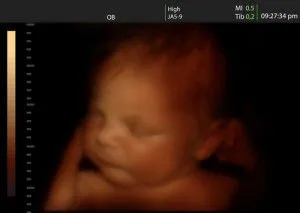

Can you imagine a so called medical professional taking a sharp instrument, and stabbing that brain in a process to murder the unborn child we are viewing above ? How much of a henious crime is that ? Ohhhh that's right, they need that child's body for stem cells, and other valuable resale items that project veritas exposed on them. My bad.